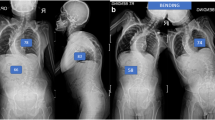

Fifty included papers described 201 individuals with SCI who developed Charcot spine. 86% of individuals had paraplegia and 93% of individuals had a neurologically complete injury. Mean length of initial spinal fusion spanned 7.7 vertebral bodies (SD = 3.9). The most common presenting symptoms were back pain (56%), spinal deformity (48%), and crepitus (34%). Vertebral body destruction (83%), osteophytes (61%), and endplate destruction (57%) were commonly reported on radiographs. Reoccurrence of Charcot spine was described in 19% of cases after initial treatment.

Charcot spine after SCI commonly presents with low back pain and radiologic evidence of vertebral body destruction. Cases have been described more often in individuals with paraplegia and neurologically complete injuries. Surgical management is often pursued. A high rate of reoccurrence of Charcot spine in individuals with SCI after initial treatment has been reported.